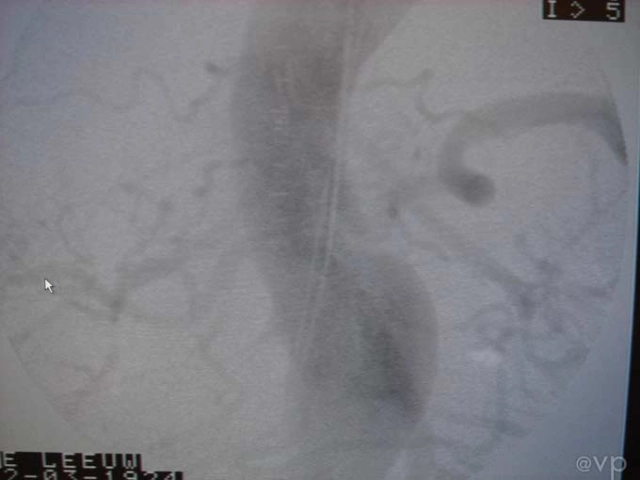

Intestinal